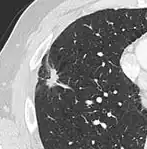

-

Low attenuating nodule (in this case a fat containing hamartoma).[9] -

Cavitation with relatively thick wall, in this case aspergilloma).[9]

- In case of calcifications, a popcorn-like appearance indicates a hamartoma, which is benign.[3]